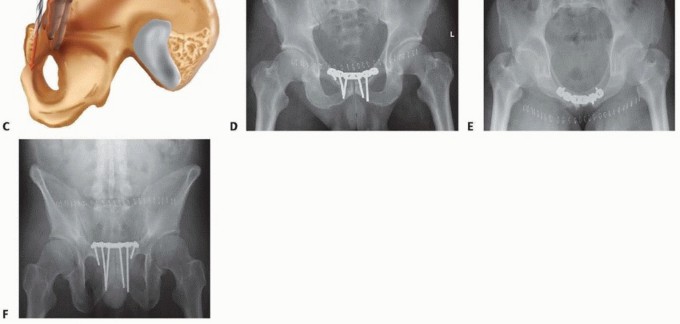

TECH FIG 5 • A. Example of how the plate needs to be contoured to accommodate the pubic tubercle on either side of the symphysis. The concavity of the plate also has to be contoured, and this can vary between genders (see FIG 2). B. Clinical photograph of plate after all screws are placed. Numbering indicates the order of screw placement, with the screws closest to the symphysis being placed first. After screws

are placed, any order may follow for the remaining screws. C. Drilling the proper angle is imperative to ensure the screw will stay in bone. To gauge the angle, one may place a finger on the posterior aspect of the pubic body and then drill parallel to that finger to ensure the drill is held at the proper angle. D-F. Postoperative AP, inlet, and outlet view radiographs of a precontoured plate and a reduced symphysis. The first screws placed are adjacent to the symphysis on either side ( TECH FIG 5B). The drill hole should be placed eccentrically, laterally in the hole to generate compression. The drill should be oriented parallel to the posterior aspect of the symphyseal body. The proper angle can be determined by using a finger to feel the inner surface of the pubic body, using it as a guide for the drill ( TECH FIG 5C). These initial screws should be angled slightly anteriorly and laterally in the pubic body so that they stay in bone and achieve the best bite. These screws can be placed to go down to the ischium if necessary. The two most medial screws on each side of the symphysis can be placed either parallel to each other or in a crossing pattern within the symphyseal body ( TECH FIG 5D-F).

TECH FIG 6 • Example of double plating described by Tile.13